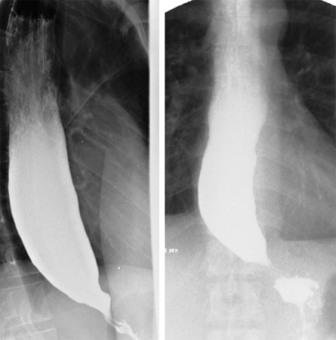

A condição mostrada no raio X abaixo é compatível com qual das seguintes manifestações?

A. Dificuldade de deglutir sólidos, mas não de líquidos

INCORRETO: O paciente geralmente queixa-se de dificuldade para deglutir sólidos e líquidos.

B. Incidência de carcinoma de esôfago acima da incidência na população normal

CORRETO : O carcinoma do esôfago é aproxirnadarnente sete vezes rnais freqüente ern pessoas portadoras de acalasia do que na população normal.

C. Incapacidade do esfíncter esofágico superior de relaxar em resposta à deglutição

INCORRETO : As características achadas no estudo de motilidade são: contrações de pequena amplitude repetitivas, que ocorrem sirnultanearnente no período de pós-deglutição ern região de corpo do esôfago; incapacidade do esfíncter inferior do esôfago de se abrir ao final da deglutição; e urna pressão acima do normal no corpo do esôfago.

D. Pressão normal no corpo esofágico

INCORRETO : As características achadas no estudo de motilidade incluem urna pressão acima do normal no corpo do esôfago.

E. Motilidade esofágica normal

INCORRETO : O diagnóstico de acalasia é geralmente suspeitado pelo esofagograrna; rnas, porque existem outras patologias de esôfago que rnirnetizarn essa condição, é necessário urn estudo de motilidade esofágica para a confirmação do diagnóstico.

Gabarito: B